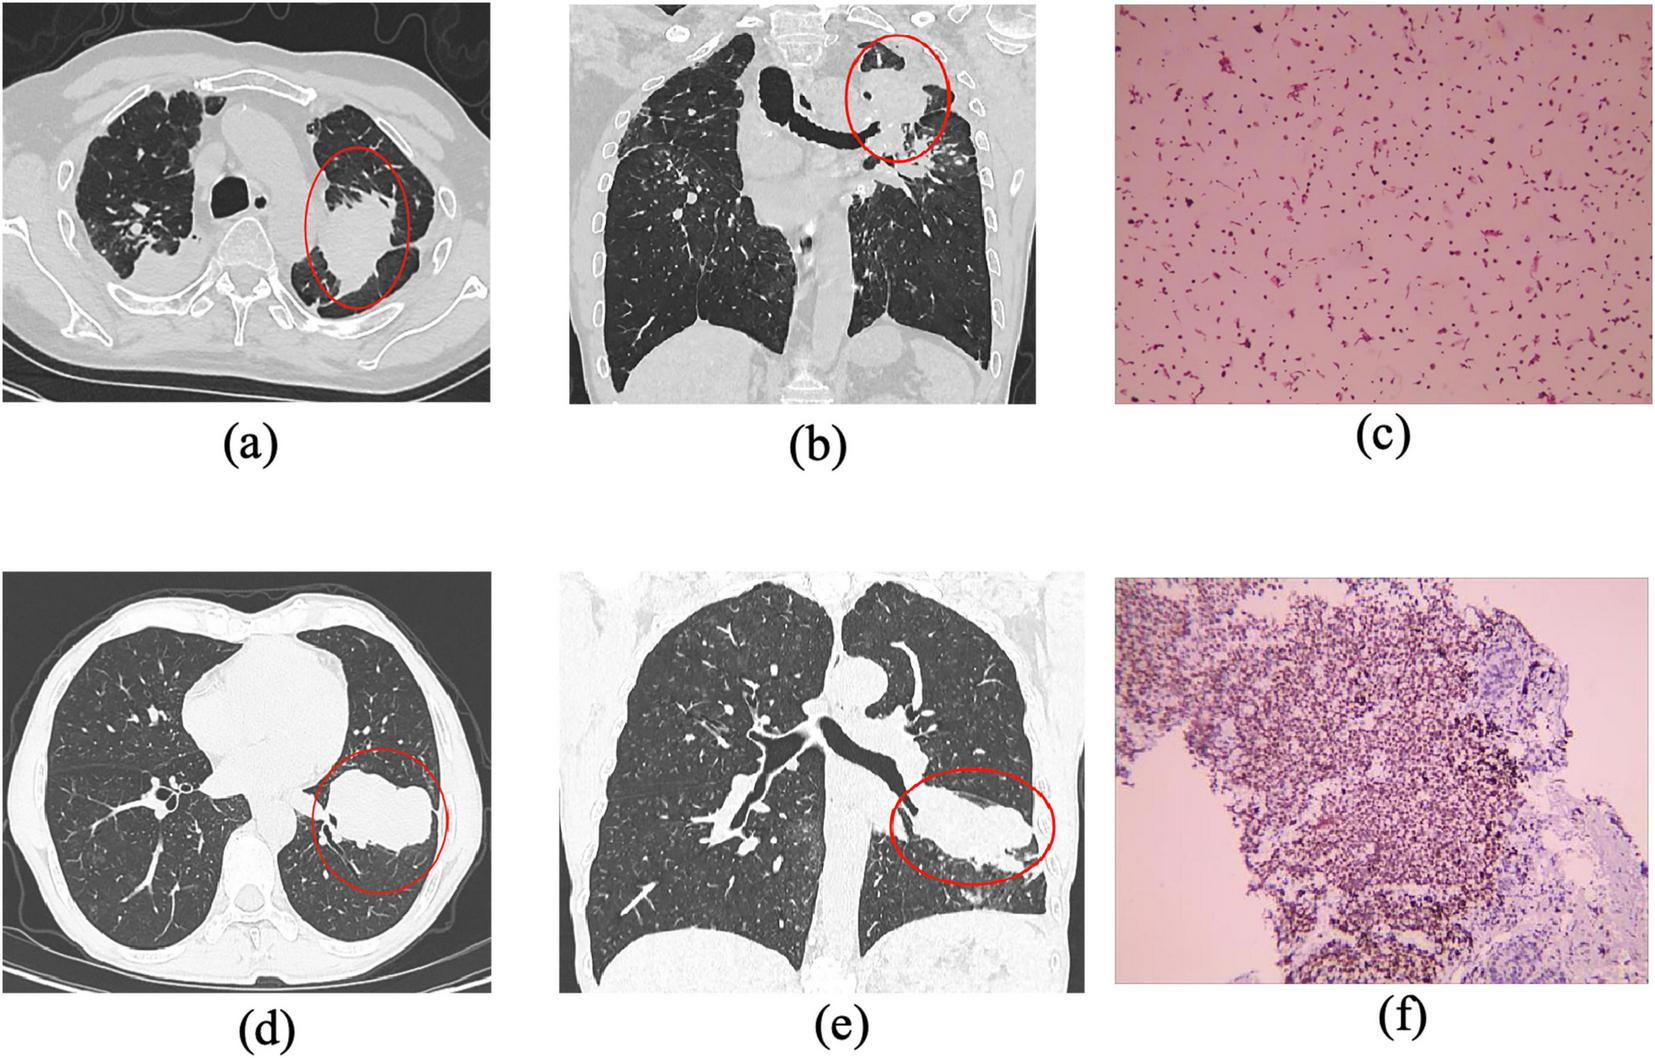

Inclusion criteria were as follows: (1) For the pneumoconiosis group: confirmed diagnosis of stage III pneumoconiosis with large opacities meeting the size thresholds (long-axis ≥ 20 mm, short-axis > 10 mm) (Figure 1; Supplementary Figure S1). (2) For the lung cancer group: confirmed diagnosis of peripheral lung cancer by both imaging and pathology, with lesions ≥ 30 mm in diameter (Figure 2; Supplementary Figure S2).

FIGURE 1

Representative CT imaging features across different stages of pneumoconiosis (axial and coronal views). (a,b) Axial and coronal chest CT images from a patient with Stage I pneumoconiosis, revealing multiple small, round, high-density nodules predominantly distributed in the upper lobes of both lungs, especially in the right upper and middle fields. (c,d) Correspond to Stage II pneumoconiosis, characterized by an increased number of opacities involving both upper lung zones and the dorsal segment of the lower lobes. (e,f) Illustrate stage III pneumoconiosis, showing a homogeneous mass-like opacity in the apicoposterior segment of the right upper lobe, accompanied by scattered calcifications, pleural thickening, adjacent localized emphysema, and nodular interstitial markings. Notably, large opacities (long-axis diameter > 20 mm, short-axis diameter > 10 mm) in advanced pneumoconiosis tend to display asymmetric distribution, suggesting progressive fibrotic remodeling of lung parenchyma.